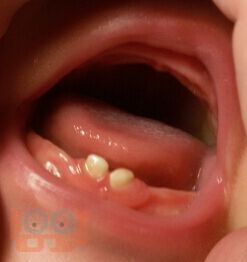

В учебном пособии представлены особенности организации и проведения в женских консультациях, в рамках школы будущих родителей, занятий по профилактике основных стоматологических заболеваний у детей первых лет жизни.

Пособие предназначено для последипломного обучения организаторов здравоохранения, врачей-стоматологов и гигиенистов стоматологических, а также для акушеров-гинекологов и психологов, работающих в женских консультациях.